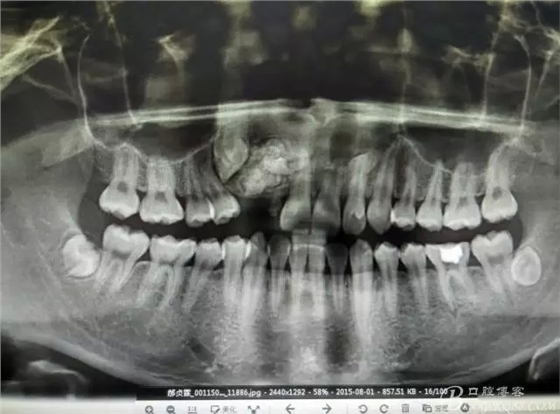

患者、郝xx、男、18歲,主訴:右側(cè)前牙未萌出,要求治療。專科檢查:右上乳Ⅱ滯留,牙冠變色,無松動(dòng)。12、13未見萌出。對側(cè)22、23正常萌出。缺牙區(qū)骨性隆起,表面不光滑,質(zhì)地堅(jiān)硬。范圍占有12、13區(qū)域。x全景片檢查:12、13阻生,其冠方有一團(tuán)2.5cmx1.8cm大小的致密團(tuán)塊,里面大小不等。不規(guī)則疑似牙齒影。診斷:牙瘤。處理:建議手術(shù) 摘除牙瘤。

圖2.全景片影像檢查:13阻生,其冠方有重疊影像,其冠方近中上方有一巨大致密鈣化團(tuán)塊。12看不見其蹤影。